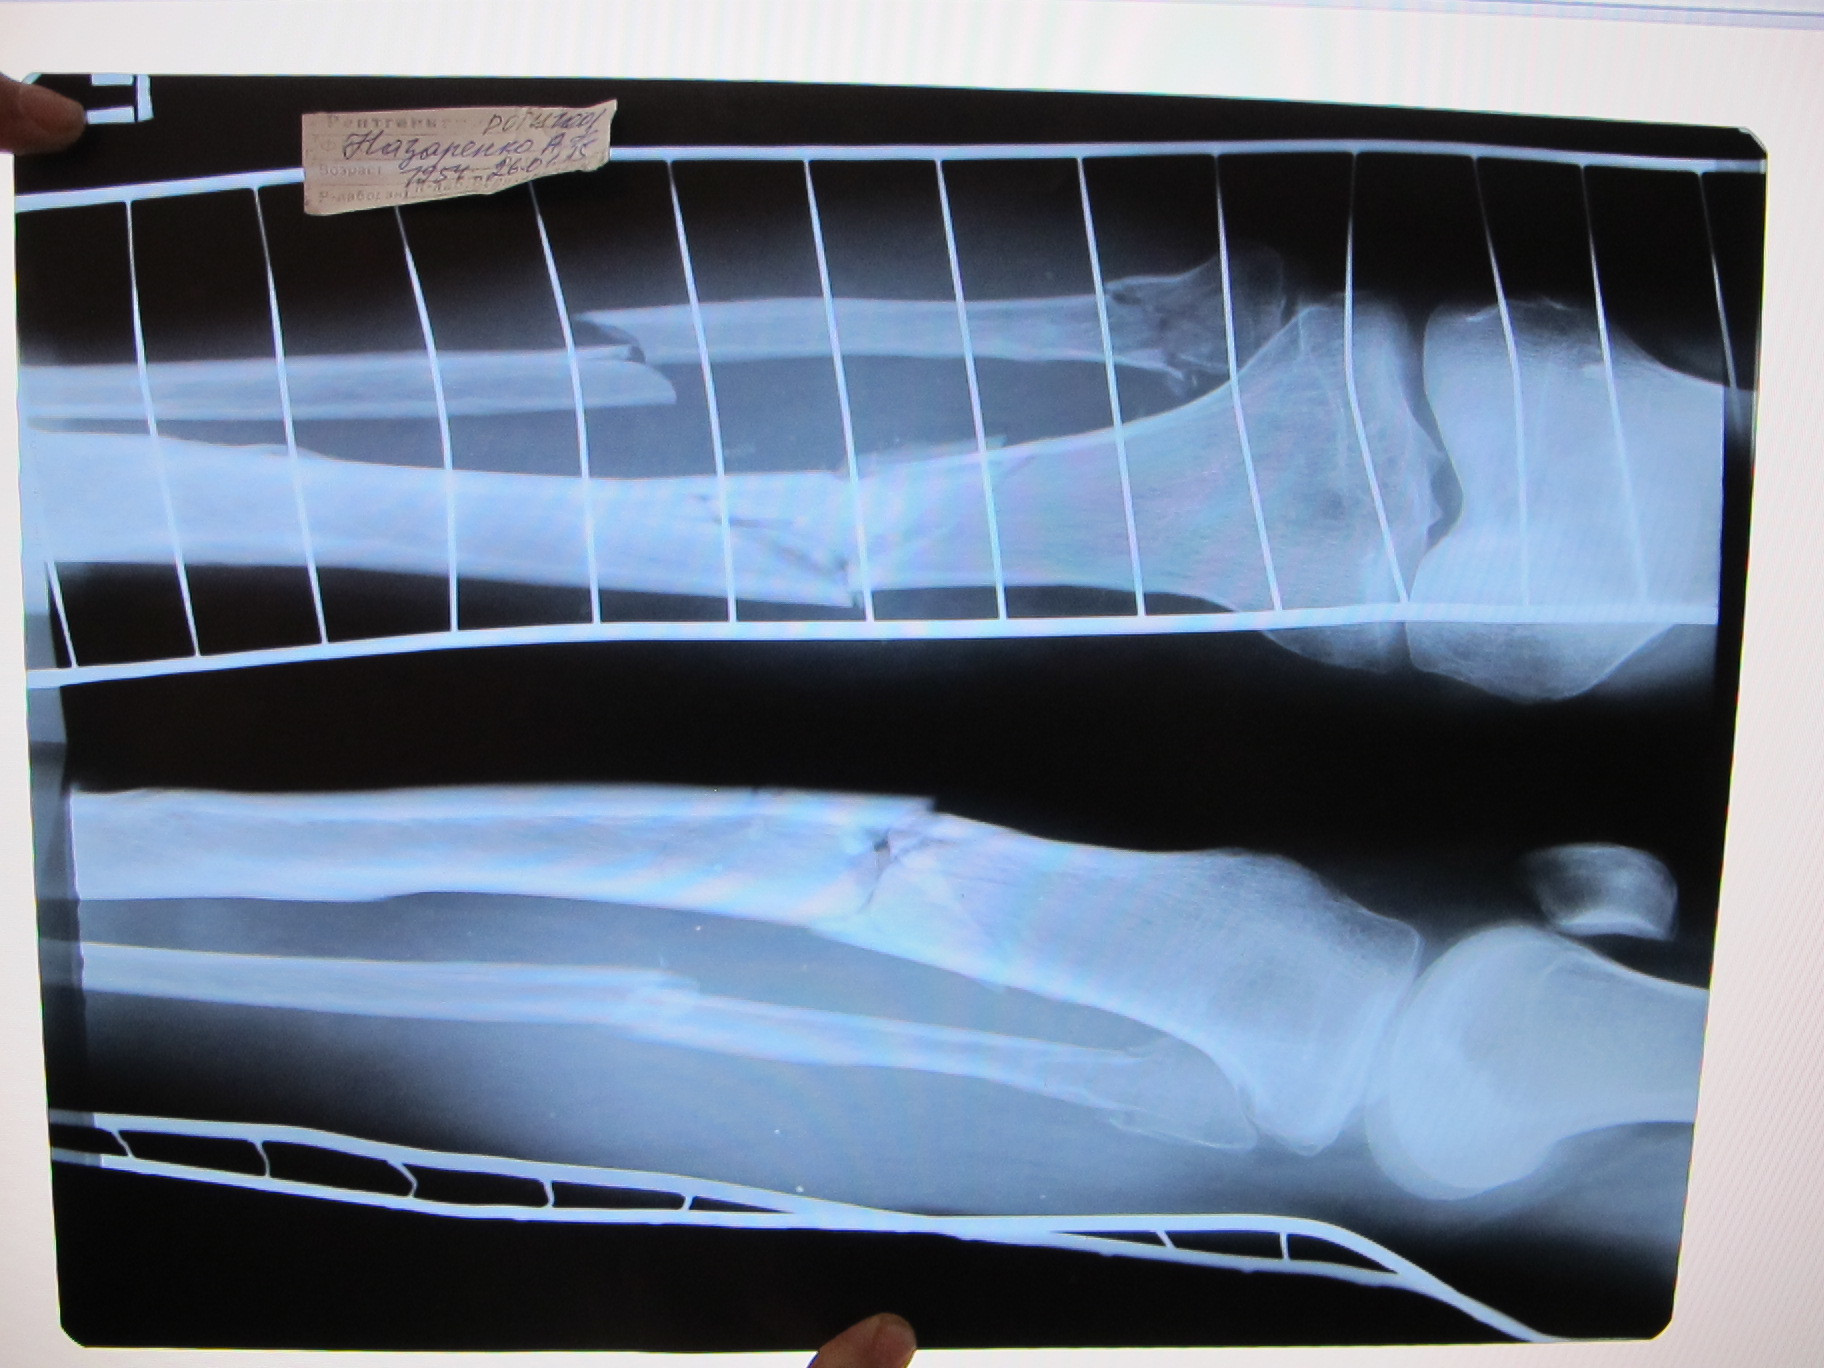

Доброй ночи. Я работаю на торговом флоте и вот 23.08 получил травму. В трав.пункте написали "перелом наружней лодыжки правой голени" положили лангету. Подскажите плиз правильный диагноз? Заранее извеняюсь за качество.

Добрый день. На представленных рентгенограммах - чрессиндесмозный перелом наружной лодыжки. Данное повреждение является нестабильным, и часто требует хирургического лечения. Но в данном случае-положение костных отломков удовлетворительное, возможно консервативное лечение. Необходимо через 7 дней после травмы выполнить рентгенограммы, и если на них положение отломков ухудшится, то тогда я бы рекомендовал выполнить остеосинтез.